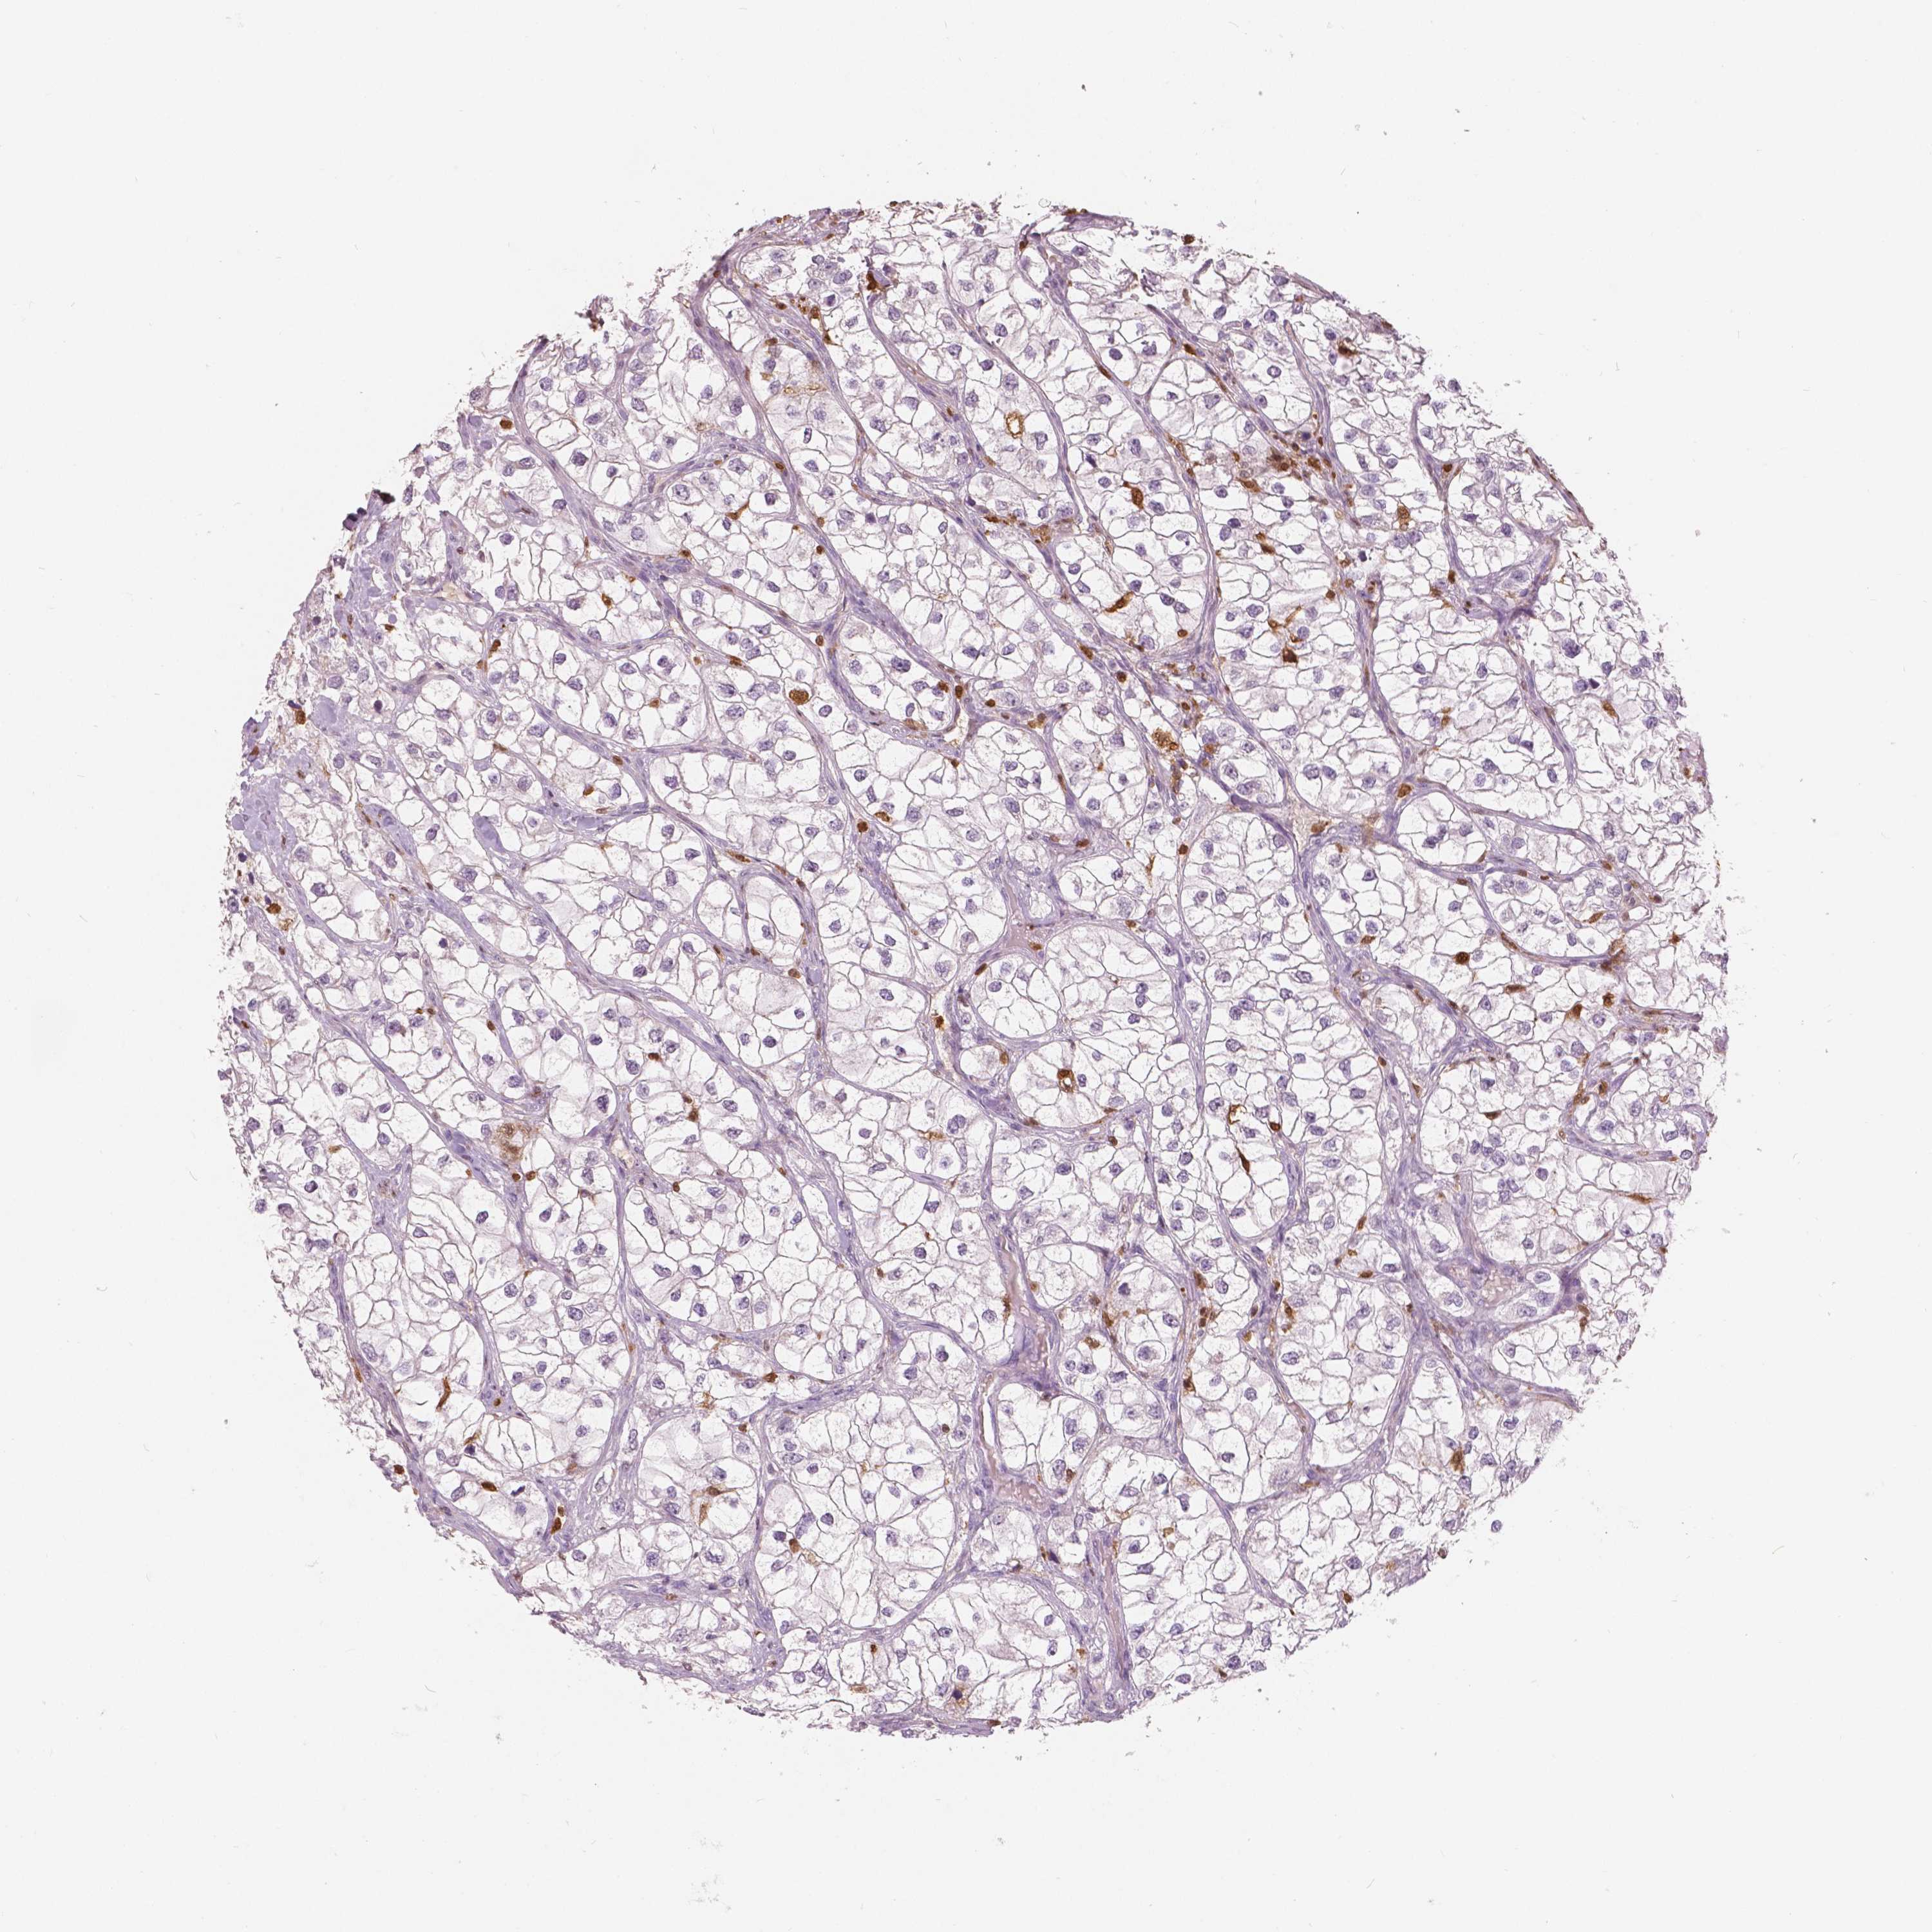

KIDNEY RENAL PAPILLARY CELL CARCINOMA (TCGA) - Interactive survival scatter ploti

The Survival Scatter plot shows the clinical status (i.e. dead or alive) for all individuals in the patient cohort, based on the same data that underlies the corresponding Kaplan-Meier plots. Patients that are alive at last time for follow-up are shown in blue and patients who have died during the study are shown in red.

The x-axis shows the expression levels (FPKM) of the investigated gene in the tumor tissue at the time of diagnosis. The y-axis shows the follow-up time after diagnosis (years). Both axes are complimented with kernel density curves demonstrating the data density over the axes. The top density plot shows the expression levels (FPKM) distribution among dead (red) and alive patients (blue). The right density plot shows the data density of the survived years of dead patients with high and low expression levels respectively, stratified using the cutoff indicated by the vertical dashed line through the Survival Scatter plot. This cutoff is automatically defined based on the FPKM cutoff that minimizes the p-score. The cutoff can be changed by dragging the vertical line or by entering a cutoff value in the square labeled "Current cut-off".

Under the Survival Scatter plot the p-score landscape (black curve; left axis) is shown together with dead median separation (red curve; right axis). Dead median separation is the difference in median mRNA expression between patients who have died with high and low expression, respectively. It is calculated as follows: median FPKM expression of dead patients with high expression - median FPKM expression of dead patients with low expression. This is intended to aid the user in visually exploring custom cutoffs and the associated p-scores and dead median separation.

Individual patient data is displayed and can be filtered by clicking on one or more of the category buttons on the top of the page. Categories describing expression level and patient information include: high, low, alive, dead, female, male and tumor stages. The scale of the x-axis can be toggled between linear and log-scale by clicking on the "x log" button. Mouse-over function shows TCGA ID, patient information and mRNA expression (FPKM) for each patient.

& Survival analysisi